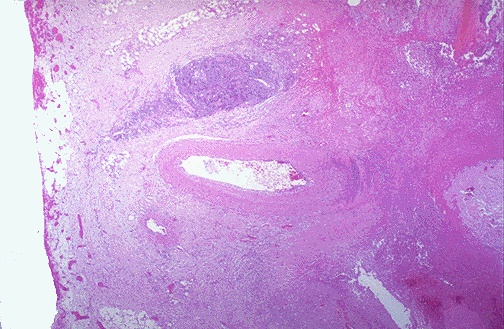

| The ulcer at the right is penetrating through the muscularis and approaching an artery. Erosion of the ulcer into the artery will lead to another major complication of ulcers--hemorrhage. This hemorrhage can be life threatening. Chronic blood loss may lead to an iron deficiency anemia. |